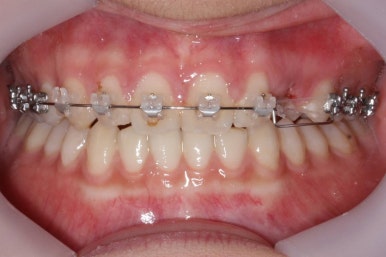

부산매복치아교정 상악 부분교정을 통해 매복치를 교정해준 이번 치료의 전후사진 비교입니다.

썩은 유치 대신 영구치 송곳니는 매우 자연스럽게 위치되었습니다. 아랫니는 교정하지 않았기 때문에 약간 삐뚠 느낌은 남아있지만 맞물림은 크게 문제가 없게 마무리 되었습니다.

얼굴 모습에서의 전후 비교입니다.

처음부터 매복치 이외에는 얼굴모습에서의 큰 문제가 없었고, 변화를 의도하지도 않았기 때문에 전후 모습의 큰 차이는 없습니다.

대신, 송곳니가 제위치되면서 웃거나 말할 때 미적으로 많이 개선된 것을 볼 수 있습니다.